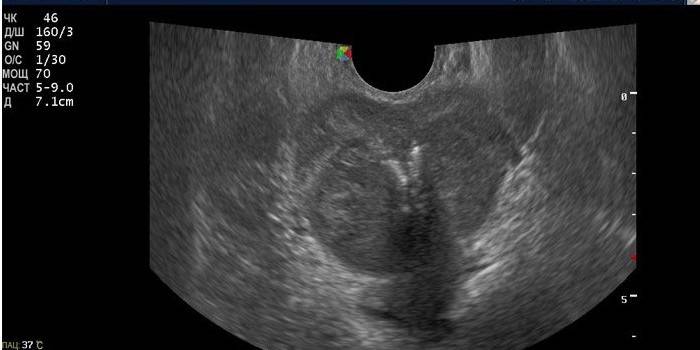

Procedura egzaminacyjna trwa 15-20 minut, czasem dłużej. Przeprowadza się to na dwa sposoby, w zależności od wskazania do badania. Nazywa się je ultrasonografem przezodbytniczym i ultrasonograficznym przezbrzusznym, które różnią się jedynie metodą prowadzenia i jakością wyniku badania.

Badanie prostaty odbywa się doodbytniczo przez odbytnicę. W tym celu stosuje się specjalny czujnik, który wkłada się do odbytu na głębokość 5-7 cm. Głowica urządzenia jest wstępnie nasmarowana żelem i pokryta folią ochronną (prezerwatywą) w celu wygodnego i sterylnego wprowadzenia. Pacjent będzie musiał trochę cierpieć. Proces ten, choć bezbolesny, jest nieprzyjemny. W przypadku przezodbytniczego badania ultrasonograficznego pacjent musi wykonać lewatywę z góry i nie jeść zabronionych pokarmów w ciągu dwóch dni.

Badanie przeprowadza się rano na czczo. W tym celu pacjent jest proszony o położenie się na kanapie po lewej stronie i zgięcie kolan do klatki piersiowej. Następnie lekarz rozpoczyna procedurę. Zaletą przezodbytniczego ultrasonografii prostaty jest jakość wyniku. Lekarz jest w stanie szczegółowo zbadać narząd i szybko postawić diagnozę. Ta opcja jest najwierniejsza i najskuteczniejsza, tylko koszt ultrasonografii przezodbytniczej jest nieco wyższy.

Po badaniu ultrasonograficznym lekarz dokonuje odniesienia do wyniku. Interpretacja ultradźwięków będzie następująca informacja. Podano tutaj dane dotyczące kształtu, ścian, struktury prostaty. Objętość narządu jest wskazana, w zdrowym stanie, którego norma wynosi 20-25 cm3, co odpowiada takim wymiarom:

- szerokość - 2,5-4 cm;

- długość - 2,5-3,5 cm;

- grubość - około 2 cm.

Za pomocą ultradźwięków określa się wagę prostaty, podczas gdy normalna waga wynosi średnio 22-26 gramów. Bez wątpienia lekarz opisa patologię, jeśli zostanie wykryta, i wskaże jej typ, rozmiar, dokładną lokalizację. Pod koniec zabiegu mężczyzna będzie mógł poznać wstępny lub końcowy wniosek, na podstawie którego urolog będzie mógł zalecić dodatkową diagnostykę lub zalecić niezbędne leczenie.